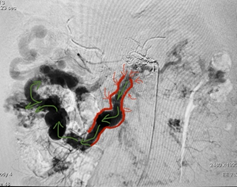

Ngay lập tức, anh T. vừa được hồi sức sốc mất máu, vừa được nhanh chóng thực hiện các phương thức hình ảnh học chẩn đoán nguyên nhân chảy máu tiêu hoá. Kết quả chụp cắt lớp vi tính (CT scan) bụng phát hiện tắc mạn tính tĩnh mạch cửa, chuyển dạng xoang hang (tái cấu trúc giãn lớn hệ thống mạch máu do tắc mạn tính) ở vùng rốn gan, nguyên nhân chính gây chảy máu là dị dạng và thông nối động – tĩnh mạch ruột lan toả gây giãn các nhánh tĩnh mạch mạc treo ruột.

| Hình đoạn ruột bệnh - Ảnh BVCC |

Trong quá trình này, vai trò của khoa Gây mê Hồi sức là vô cùng quan trọng. Đặc biệt, trong việc duy trì ổn định huyết áp cho người bệnh. Đầu tiên, các bác sĩ phẫu thuật tiêu hoá mở bụng và bộc lộ vị trí dị dạng mạch máu để tạo thuận lợi cho bác sĩ X quang can thiệp tiếp cận làm tắc đoạn tĩnh mạch bệnh lý, giúp giảm áp lực hệ tĩnh mạch cửa và qua đó, cuộc mổ có thể được kiểm soát mất máu dễ dàng hơn.

Tiếp theo, bác sĩ phẫu thuật mạch máu tạo cầu nối từ hệ tĩnh mạch cửa sang hệ tĩnh mạch chủ nhằm làm giảm tối đa áp lực của hệ tĩnh mạch cửa. Cuối cùng, bác sĩ phẫu thuật tiêu hoá tiến hành cắt bỏ gần 3 mét ruột non chứa dị dạng mạch máu để đảm bảo kiểm soát chắc chắn tình trạng chảy máu tái phát sau mổ và nối ghép phần còn lại để phục hồi lưu thông ruột”.